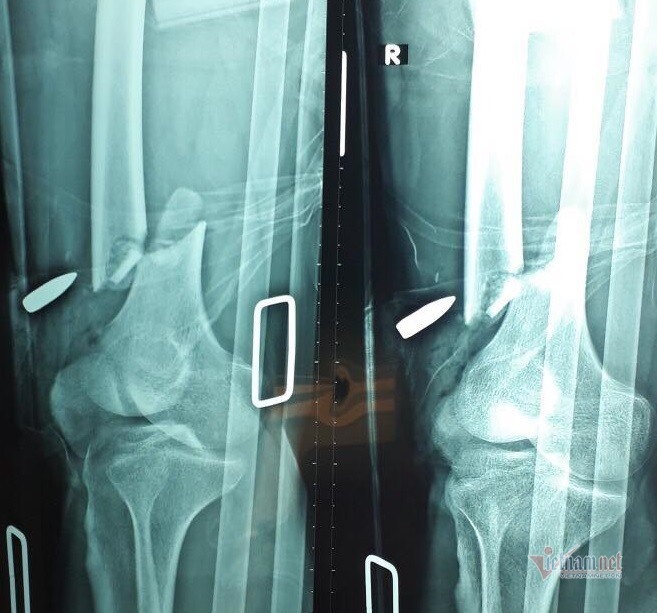

| Ảnh chụp X-quang cho thấy đầu đạn ghim vào đùi phải nạn nhân. Ảnh: Hòa Khánh |

Ê-kíp đã tiến hành lấy viên đạn ra khỏi đùi, tiến hành mổ cắt lọc vết thương, nối gân cơ đùi và khâu khôi phục từng lớp... Hiện, bệnh nhân sức khỏe ổn định và được theo dõi nhiễm trùng vết thương.